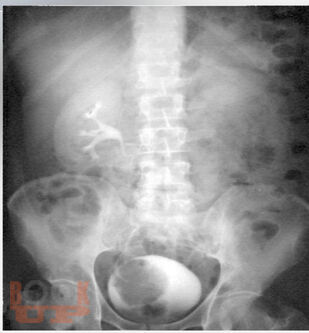

Учебное пособие содержит современную характеристику факторов риска развития рака мочевого пузыря (РМП), что позволит из общей массы амбулаторно-поликлинического приёма более чётко выделять тех пациентов, у которых имеется высокий риск развития онкопатологии. Рассмотрены важные клинические симптомы различных вариантов РМП, методы диагностики, лечения и профилактики, направленные на повышение онкологической настороженности среди врачей и населения. Предложенные авторами алгоритмы обследования больных в амбулаторном звене при первичном обращении пациента подчинены единой концепции и дают возможность индивидуализировать, упорядочить и контролировать работу по своевременной диагностике раковых заболеваний.